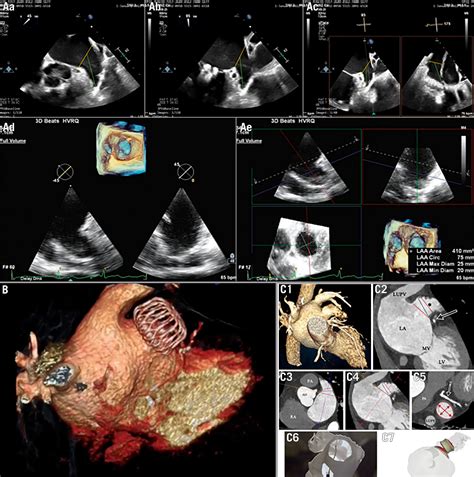

1. Pre-procedural Imaging: Using a Transesophageal Echocardiogram (TEE) to visualize the LAA and ensure it is free of existing clots.

4. Deployment: The occlusion device is deployed to perfectly fit the dimensions of your LAA.

Recovery following Left Atrial Appendage Occlusion is generally swift. Patients are typically advised to avoid heavy lifting or strenuous activity for a few days to allow the groin access site to heal. Over the following weeks and months, a follow-up imaging appointment is usually scheduled to confirm that the device remains in the correct position and that no leaks are present around the edges.

Most patients continue taking a blood thinner or antiplatelet medication for a short window (usually 45 days to six months) following the implant. This allows the heart lining to grow over the device, creating a smooth, natural surface inside the heart. Once the physician confirms complete occlusion, the need for blood thinners is often eliminated or significantly reduced, marking a major milestone in the patient's long-term cardiovascular health strategy.